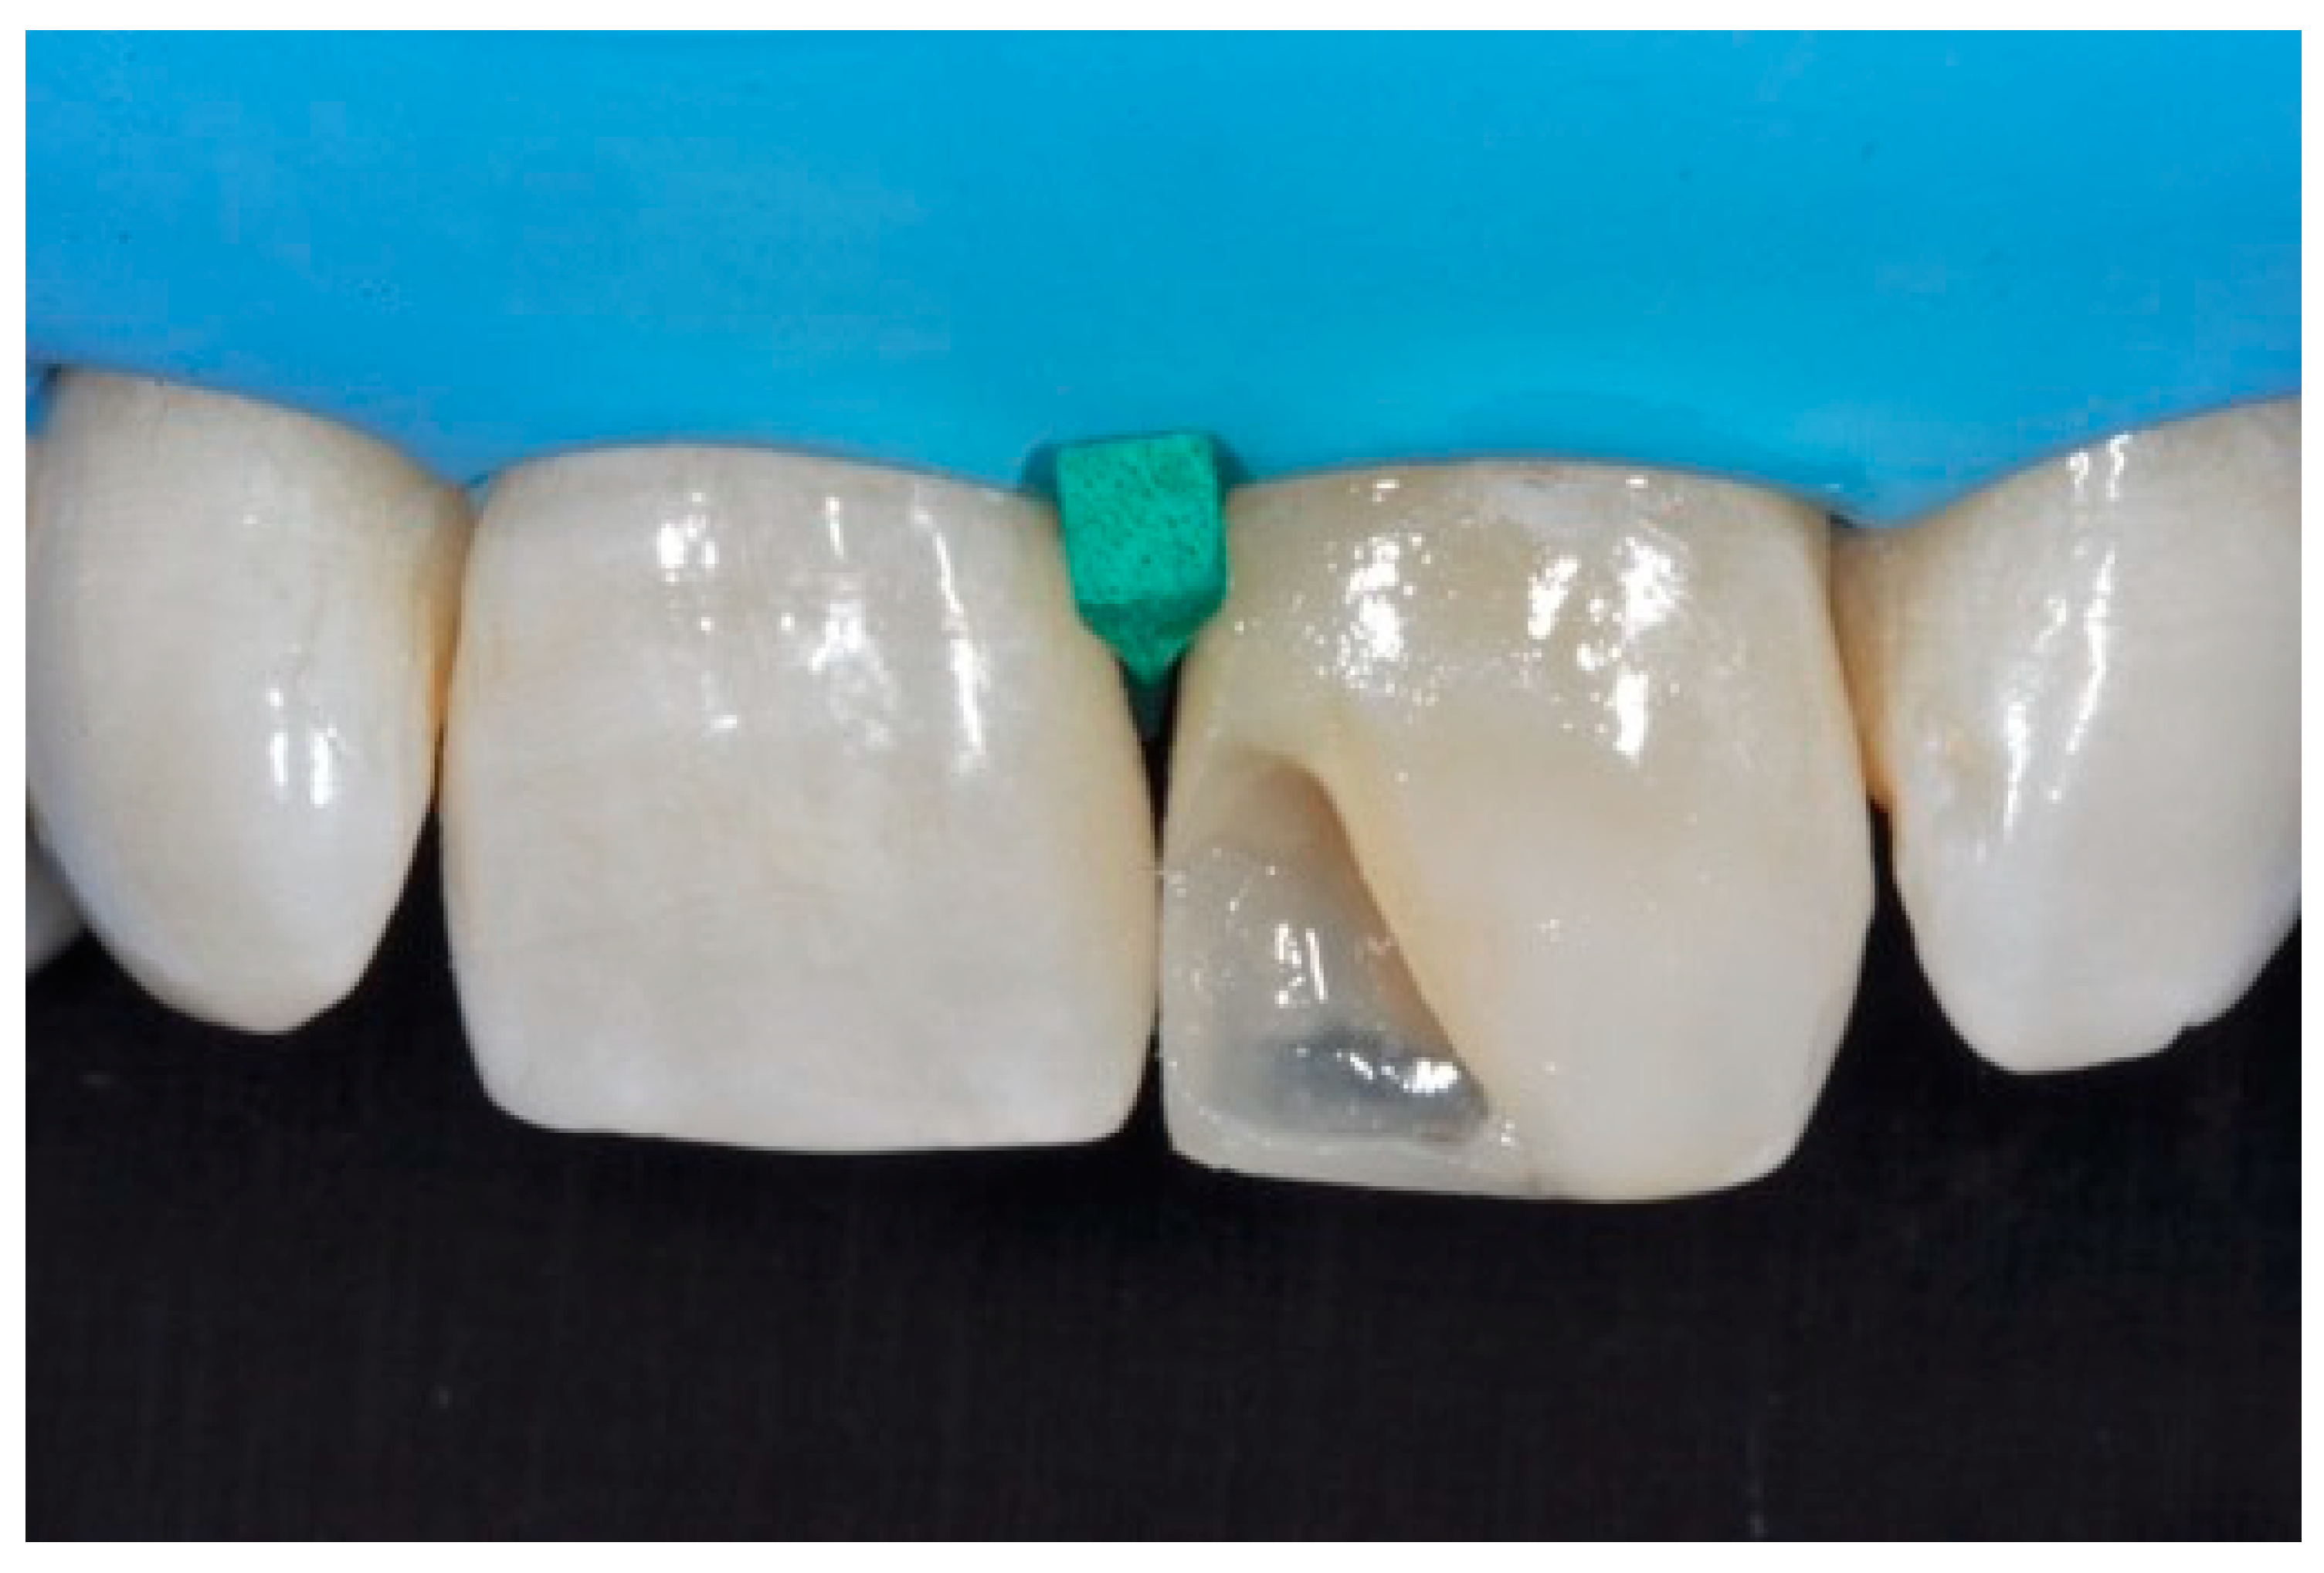

Once completed, the two frames (Clearfil Majesty ES-2, A1E, A2D, Kuraray Noritake Dental, Tokyo, Japan) showed internal and external excesses that were reduced using diamond burs and discs (Figure 33 and Figure 34) strictly following the procedure described in Section 2.1.2 of present article. Excesses were removed from the distal-incisal angle of #2.1 allowing therefore to obtain the desired translucency. After silane application and bonding procedure (Figure 35) as described in Section 2.1.2, restorations were completed (Figure 36 and Figure 37). They both show satisfactory clinical integration 1.5 years post-operative (Figure 38 and Figure 39).

Figure 33.

Frame imprecisions are corrected by reducing interproximal wall from the internal side. Reprinted from Restauri diretti nei settori anteriori, G. Paolone, S. Scolavino, © 2021, with permission from Quintessence Publishing Italy.

Figure 34.

Frame is also trimmed reducing external outline. Reprinted from Restauri diretti nei settori anteriori, G. Paolone, S. Scolavino, © 2021, with permission from Quintessence Publishing Italy.

Figure 35.

The modified frames treated with silane coupling agent and adhesive, ready for layering of dentinal body. Reprinted from Restauri diretti nei settori anteriori, G. Paolone, S. Scolavino, © 2021, with permission from Quintessence Publishing Italy.